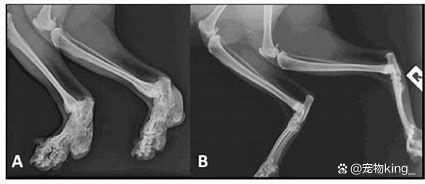

数据显示,多达90%的老年猫咪在X光检查时显示有关节炎的迹象,但大多数主人并不知情。为了减轻关节炎带来的痛苦,保持猫咪的健康体重是关键。

即使是一两磅的超重也会显著增加关节负担。

兽医可以帮助你制定长期的疼痛管理计划,包括药物、补充剂以及针灸、物理治疗和激光治疗等替代疗法。